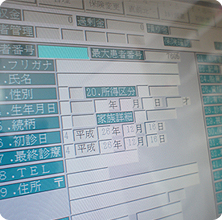

デジタルレントゲンシステム

被ばく最大幅減少

電子カルテシステムで

分かりやすい説明